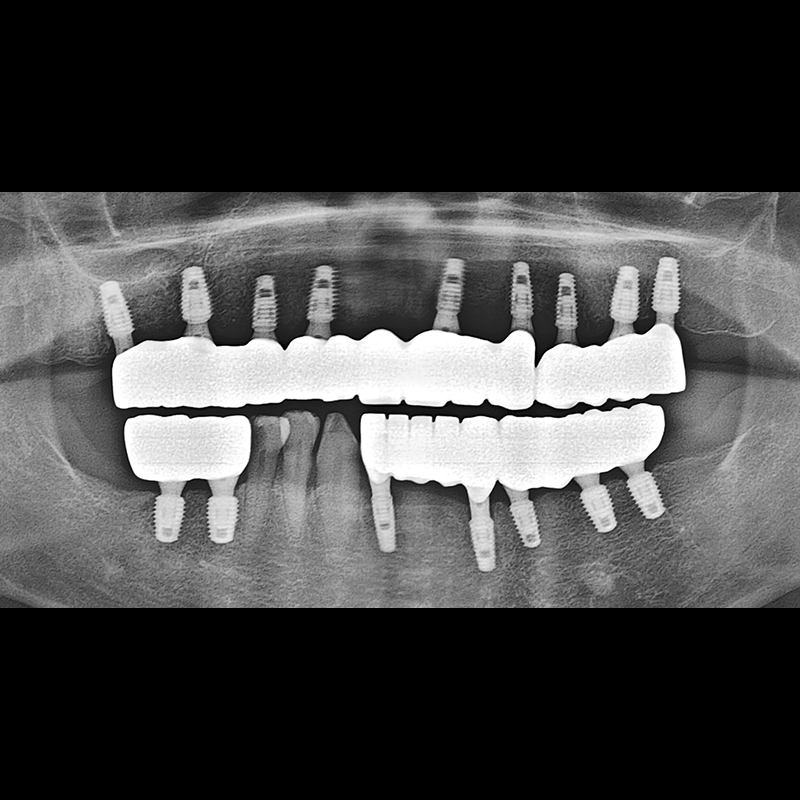

BEFORE AFTER

임플란트 전후사진 2025.05.30

결손된 치아 부분과 살리기 힘든 치아 위치에 임플란트를 식립하였습니다.